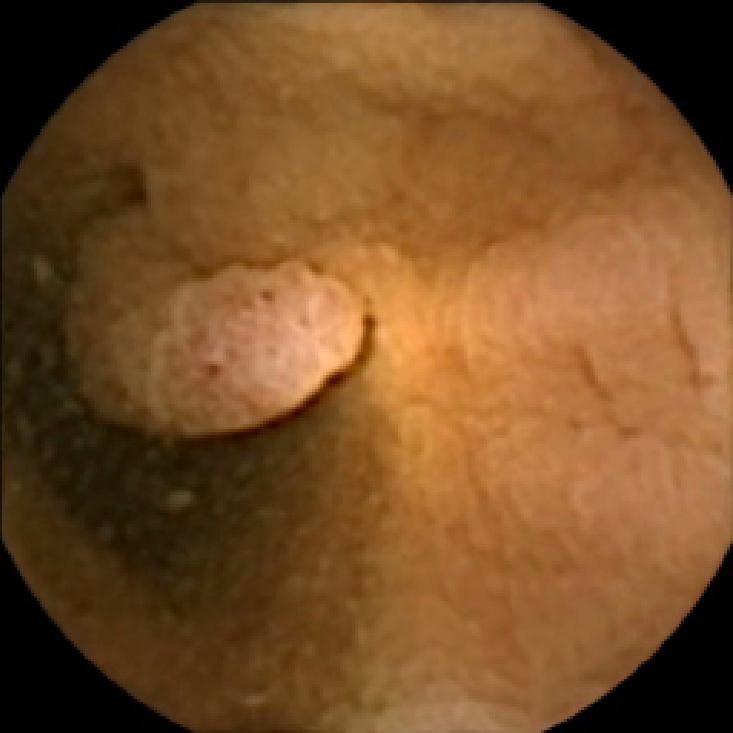

In Figure 5 we show the circles of radius corresponding to the features that were correctly classified as polyps by (29). We observe that the classifier was able to identify the polyps of a variety of shapes even in the presence of small amounts of trash liquid (first row) or when the polyps are located next to mucosal folds (rows two to four in column (c)).

The examples of incorrect classification of frames are presented in Figure 6. The first two examples show false negatives, each highlighting a possible source of classification error. The example in column (a) shows the case where the feature corresponding to the polyp was too stretched out and thus was rejected by the eccentricity criterion (21). In contrast, the feature corresponding to the polyp in column (b) has passed the combined geometric criterion (22), but the radius was below the threshold of the binary classifier. Examples in columns (c) and (d) show the two sources of possible false positives. The false positive detection in column (c) is due to insufficient illumination correction. The bright spot is not fully corrected at the pre-processing stage and subsequently generates a polyp-like feature in the mid-pass filtered frame that happens to pass through all the criteria. Finally, in column (d) a mucosal fold is classified as polyp. Note that such cases are the most difficult to deal with, as the mucosal folds can often be hard to distinguish from polyps even for a human operator.